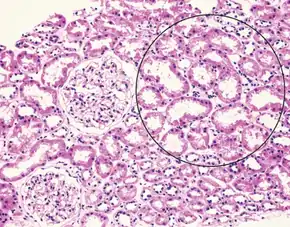

| Liver histology is altered in HRS while kidney histology is normal. The upper image is a trichrome stain (chicken wire appearance) of cirrhosis of the liver, the most common cause of HRS. | |

Those affected usually have cirrhosis, though it may also occur in alcoholic hepatitis or liver failure.[1] Additional risk factors include low blood pressure and low sodium.[1] Onset may be triggered by infection, gastrointestinal bleeding, overuse of diuretics, draining ascites (fluid in the abdomen), surgery, or medications like ACE inhibitors.[1][2] The underlying mechanism involves liver problems precipitating insufficient blood flow to the kidneys.[1] The kidneys are otherwise normal.[2] Diagnosis is based on laboratory tests of kidney function, after ruling out other possible causes.[2] Type 1 includes a rapid decline in kidney function, while type 2 is associated with ascites that does not improve with diuretics.[2]

Hepatorenal syndrome usually affects individuals with cirrhosis and elevated pressures in the portal vein system (termed portal hypertension). While HRS may develop in any type of cirrhosis, it is most common in individuals with alcoholic cirrhosis, particularly if there is concomitant alcoholic hepatitis identifiable on liver biopsies.[5] HRS can also occur in individuals without cirrhosis, but with acute onset of liver failure, termed fulminant liver failure.[7][5]

Many other diseases of the kidney are associated with liver disease and must be excluded before making a diagnosis of hepatorenal syndrome. Individuals with pre-renal kidney failure do not have damage to the kidneys, but as in individuals with HRS, have kidney dysfunction due to decreased blood flow to the kidneys. Also, similarly to HRS, pre-renal kidney failure causes the formation of urine that has a very low sodium concentration. In contrast to HRS, however, pre-renal kidney failure usually responds to treatment with intravenous fluids, resulting in reduction in serum creatinine and increased excretion of sodium.[7] Acute tubular necrosis (ATN) involves damage to the tubules of the kidney, and can be a complication in individuals with cirrhosis, because of exposure to toxic medications or the development of decreased blood pressure. Because of the damage to the tubules, ATN affected kidneys usually are unable to maximally resorb sodium from the urine. As a result, ATN can be distinguished from HRS on the basis of laboratory testing, as individuals with ATN will have urine sodium measurements that are much higher than in HRS; however, this may not always be the case in cirrhotics.[18] Individuals with ATN also may have evidence of hyaline casts or muddy-brown casts in the urine on microscopy, whereas the urine of individuals with HRS is typically devoid of cellular material, as the kidneys have not been directly injured.[7] Some viral infections of the liver, including hepatitis B and hepatitis C can also lead to inflammation of the glomerulus of the kidney.[19][20] Other causes of kidney failure in individuals with liver disease include drug toxicity (notably, the antibiotic gentamicin) or contrast nephropathy, caused by intravenous administration of contrast agents used for medical imaging tests.[7]